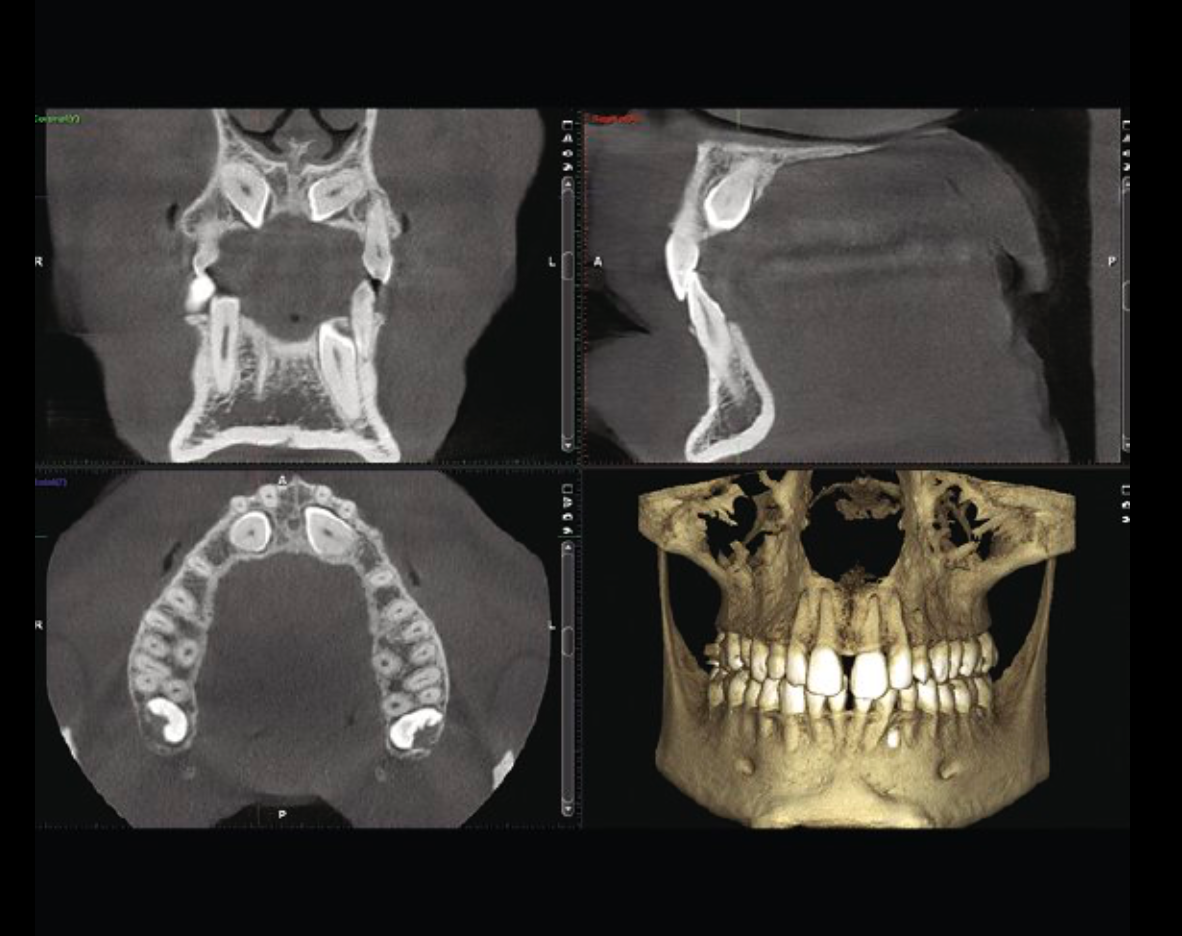

Calidad de imagen excepcional

Equipadas con soluciones y algoritmos inteligentes de alta tecnología, todas nuestras unidades de procesamiento de imágenes dentales 3D ofrecen un proceso de imágenes sin esfuerzo e imágenes nítidas, también a dosis bajas. Las unidades se han diseñado para evitar errores humanos en el procesamiento de imágenes CBCT, con opciones disponibles para corregir el movimiento, reducir los artefactos y eliminar el ruido.